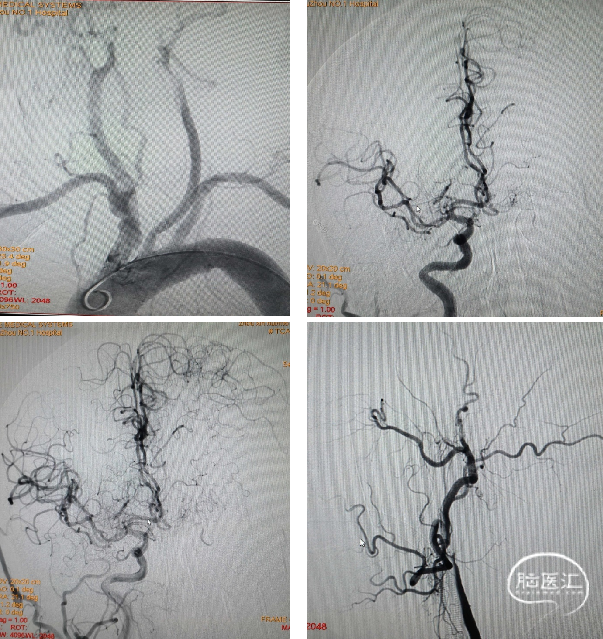

穿刺右侧股动脉,植入8F血管鞘,造影发现左侧颈内动脉闭塞,右侧颈内动脉经前交通动脉、大脑前动脉代偿供血。

泥鳅导丝导引将8F导引导管置入左侧颈总动脉末端,送入6F中间导管,微导丝导引微导管送至颈内动脉远段,冒烟显示眼动脉以下颈内动脉显影,但血管内充盈缺损明显,以上血管未显影。6F中间导管无法通过颈内动脉起始部,提示串联病变:颈内动脉起始部重度狭窄,狭窄以上管腔内大量血栓形成。采用4*30mm球囊扩张颈内动脉起始部,跟进中间导管,抽出大量血栓,但远段血管仍不显影,考虑大脑中动脉闭塞。

微导丝探查至大脑中动脉M2段,跟进微导管,“冒烟”显示远端通畅。边缓慢回撤微导管,边“冒烟”显示M1段造影剂充盈缺损,呈“轨道征”表现,表明血栓位于该处。

将Reco 4*20mm取栓支架送入血栓处,支架释放5min后,中间导管连接50ml注射器负压抽吸,撤出支架,成功拉出血栓。再次造影显示大脑中动脉M1段开通,但血管壁毛糙明显,经中间导管推注替罗非班7ml避免内膜损伤急性血栓形成。

替罗非班经静脉7ml/h维持,10min后经导引导管于颈总动脉造影显示:颈内动脉起始部重度狭窄,远段血通畅,(mTICI评分3级)。为降低风险,决定二期处理颈内动脉狭窄。